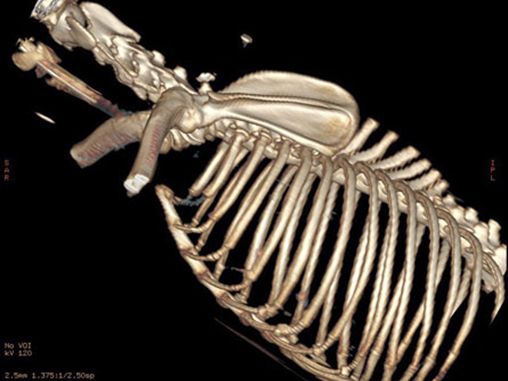

Because the technique uses a very fine beam of Xrays detected by a fine array of sensors a 3D picture can be built up of the subject being examined. There are three types of CT, helical, linear and cone beam, helical and linear provide the greatest image quality allowing detailed imaging of patients as large as a Great Dane’s chest to as small as a kitten’s foot.

The inherent contrast afforded by the differences between, air, bone, fat and soft tissue is also enhanced by the use of Iodinated intravenous or intra arterial contrast (intravenous being the most common) and so very fine detail of tomography, internal architecture and vascular supply and drainage is possible for bones, the abdomen, the chest, head and neck in fact almost every body part. Only brain, spinal cord and muscular tendinous injuries are areas where MRI may provide superior imaging.

CT scanning is as rapid as routine radiography and in many cases quicker and has proved to be invaluable to the improved diagnostics for orthopaedic disease and injuries for cats and dogs, especially in elbow dysplasia and patella luxation where the improved diagnostics are making our treatments more accurate with improved functional outcomes and reduced complications.